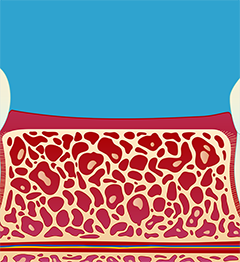

1.) Innsetting av implantat (fikstur) (fig. I-II). Operasjonen utføres under lokalbedøvelse. Etter inngrepet vil man motta mer utfyllende informasjon. Slik vet man hvordan man skal forholde seg i tiden etter operasjonen.